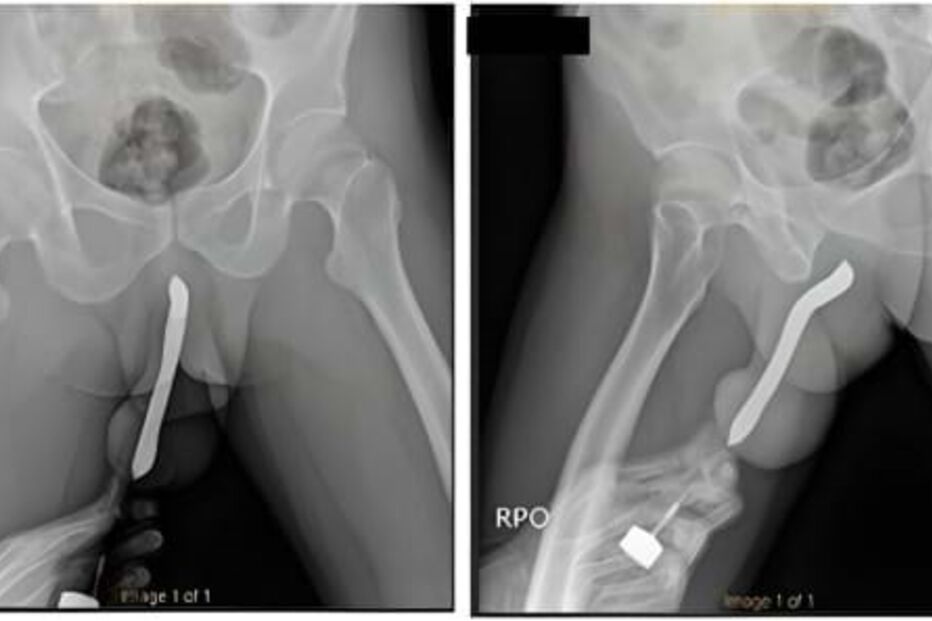

Um homem, de 43 anos, fraturou o pénis durante a atividade sexual com uma mulher depois de uma escova de dentes, que tinha inserida no órgão genital, se ter partido, de acordo com o DailyMail.

Apesar das dores, só procurou ajuda médica 12 horas depois. Feito o diagnóstico, o homem foi operado durante duas horas no Hospital Geral Académico de Soetomo, em Java Oriental, Indonésia, para reparar a fratura.

Segundo o próprio, quando questionado pela equipa médica sobre o que aconteceu, contou que em 2017 fez uma pequena cirurgia para colocar uma escova de dentes no órgão genital com o objetivo de ter maior "satisfação sexual".

Três dias após a cirurgia o paciente teve alta. Não surgiram outras complicações.